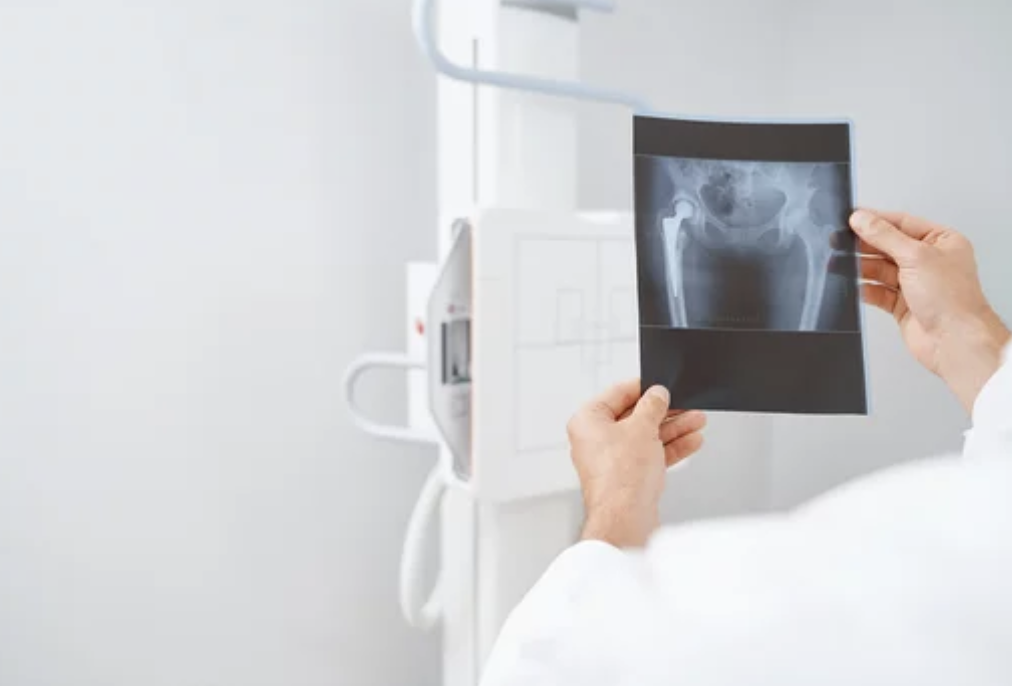

고관절 통증의 진단과 치료는 의사의 전문적인 평가와 조언이 필요합니다. 의사는 환자의 증상을 평가하고 필요에 따라 신체 검사나 영상 검사를 통해 진단을 내릴 수 있습니다. 관절염 등의 염증성 질환인 경우 항염증 약물이나 생활습관의 변화를 통한 관리가 필요합니다. 골관절탈구나 심한 손상의 경우 수술이 필요할 수 있습니다. 물리치료나 침술 등의 보조 요법도 통증을 완화하는 데 도움이 될 수 있습니다.